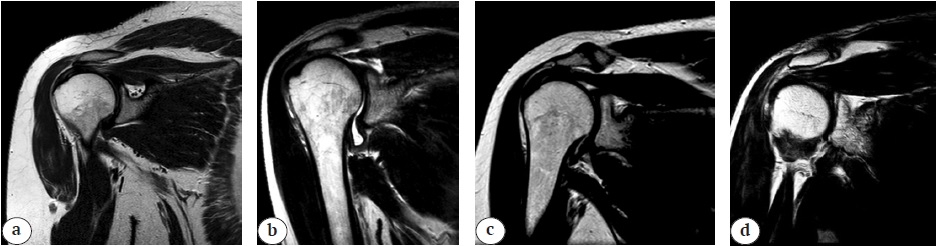

В ходе исследования была установлена корреляция морфологии надлопаточной вырезки с патологией надлопаточного нерва и структурой повреждений вращательной манжеты. На рисунке 1 представлены примеры различных типов надлопаточной вырезки по Rengachary.

Рисунок 1. Примеры типов надлопаточной вырезки по классификации Rengachary: a — тип I; b — тип II; c — тип III; d — тип IV; область надлопаточной вырезки оценивали в косо-коронарной проекции в режиме Т2 TSE